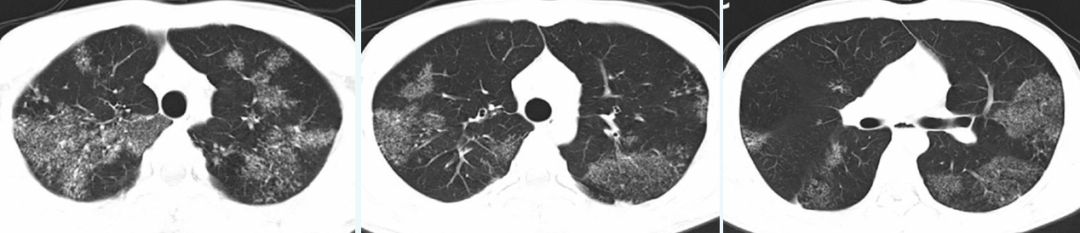

病例1:

从这张影像可以看到相对光滑的反晕征(红色箭头处)。患者为52岁女性,类风湿关节炎史,发热咳嗽,肺部病变经穿刺活检为OP。2015-1-20(左上)这团病灶相对比较致密,经过三周,2015-2-10(右上),如红色箭头处,它有所扩大,但中央明显变淡了,看起来质地特别光滑。